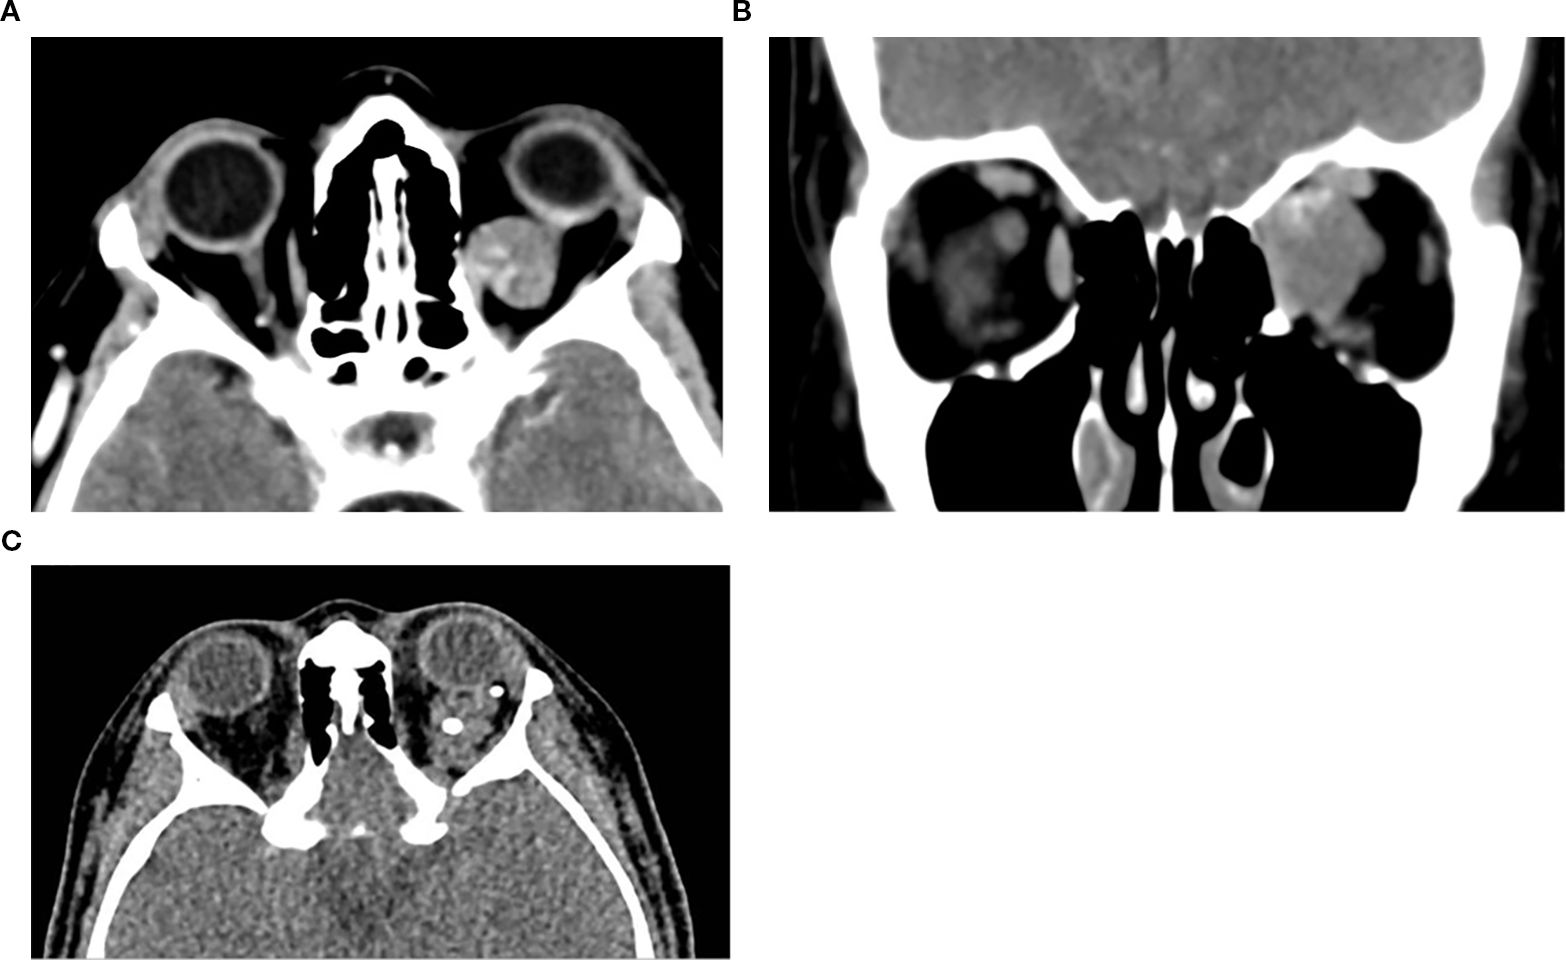

Orbital masses include a diverse spectrum of benign, malignant, inflammatory, and vascular lesions in pediatric and adult patients. Accurately diagnosing the type of lesion is critical, as management strategies differ significantly. Advanced imaging is therefore essential, and computed tomography (CT) is central to orbital evaluation. We reviewed the literature to synthesize evidence on CT features across common orbital pathologies and correlated imaging with clinical presentation to emphasize diagnostic relevance. CT characteristics are summarized for vascular lesions (cavernous venous malformation, lymphatic malformation), inflammatory conditions (orbital myositis, dacryoadenitis), benign lesions (dermoid cyst, pleomorphic adenoma), and malignant lesions (lacrimal gland lymphoma, adenoid cystic carcinoma, rhabdomyosarcoma). We present characteristic patterns of location, morphology, enhancement, and bone change, with practical discriminators and common pitfalls to aid differentiation. When used alongside clinical context, CT remains a preferred modality in many clinical settings due to its rapid acquisition, wide availability, and reliable depiction of bone and calcifications. It supports accurate diagnosis and informed management decisions in time-critical settings. This review provides a structured reference for interpreting CT findings across a wide range of orbital disease.